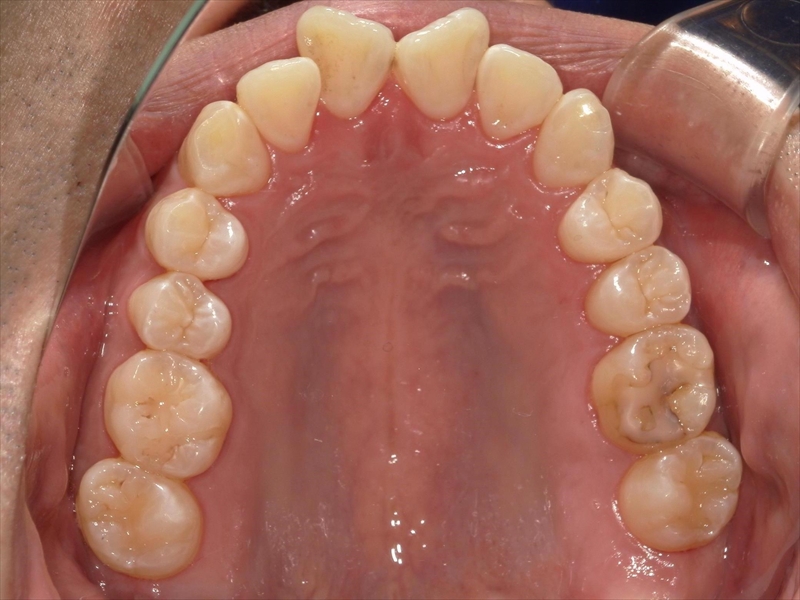

上顎について

前歯のねじれ(V字)と出っ歯を下げるスペースを確保のため、両側1~5番目を0.2~0.5ミリ(計4ミリ)削ることと、奥歯から順に奥へ下げながら外側へ広げる計画を立案しました。

患者様の努力(マウスピース装着時間確保、MFT)もあり、きれいに並べることができました。

治療前後 写真